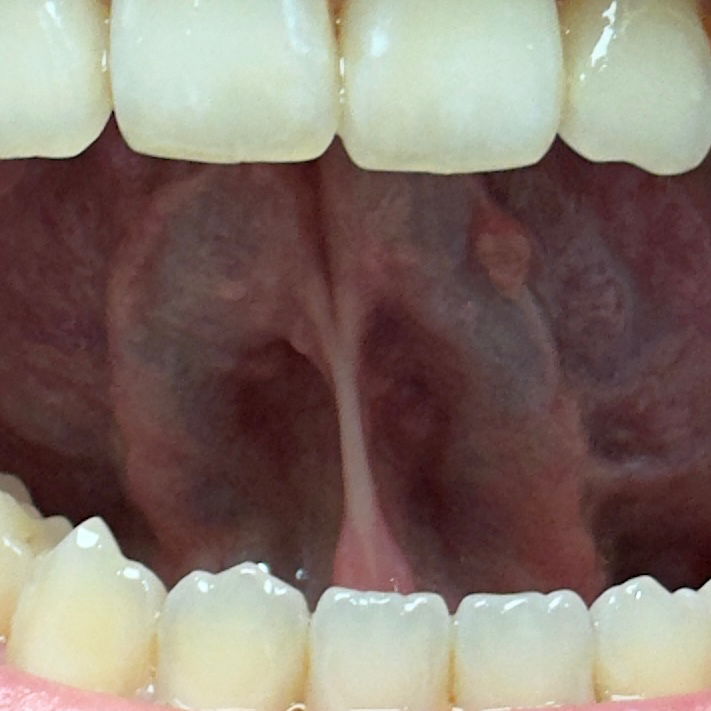

혀 아래,밑부분에 돌기?뾰루지? 같은게 있습니다

혀 밑부분에 돌기나 뾰루지 같은게 있는데요.

(사진은 좀 흐릿하게 나온편입니다)

예전부터 있었는지,최근에 생긴건지는 모르겠습니다.

1. 병원에 꼭 가봐야 하는 질병일까요??

2.악성 종양일 가능성이 있을까요??

• 1번 째 사진